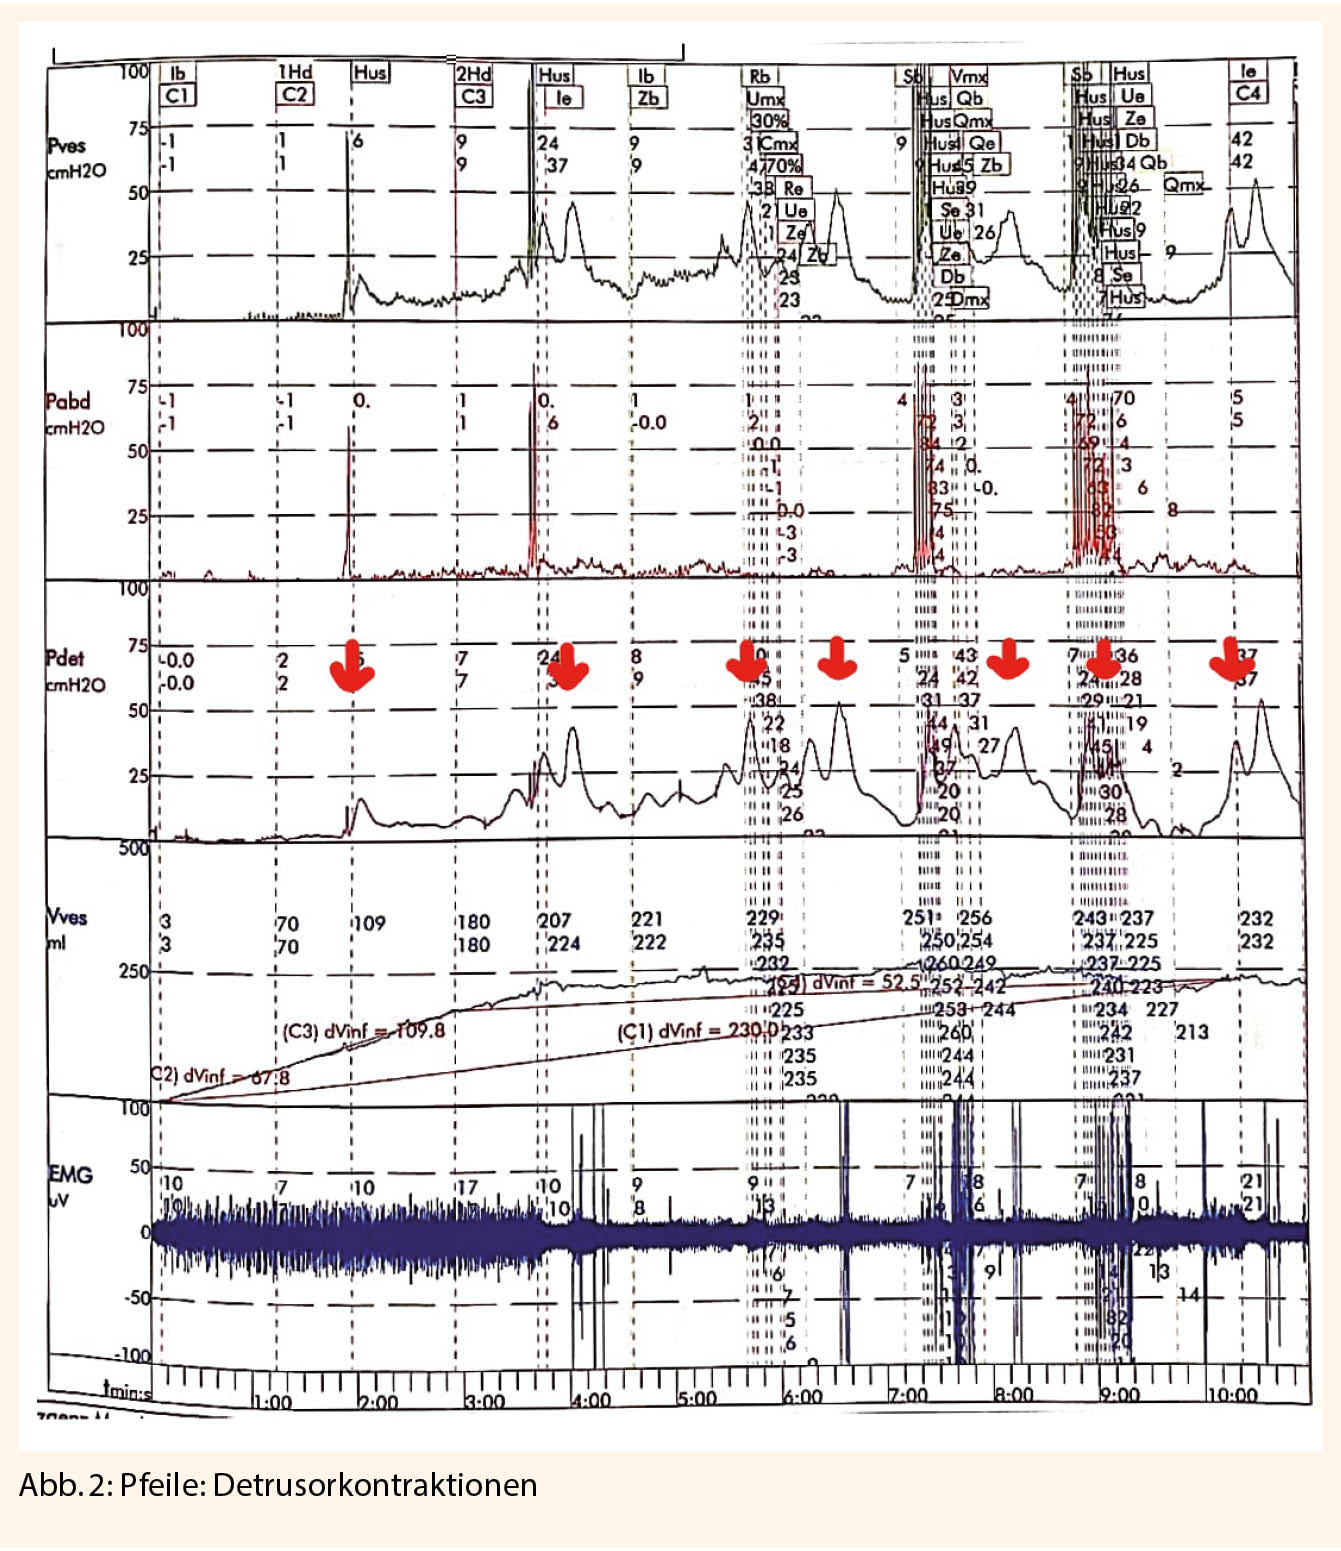

Über den gesamten Untersuchungszeitraum werden kontinuierlich der intravesikale Druck und der abdominelle Druck registriert. Über den transurethralen Katheter wird der intravesikale Druck gemessen. Durch eine rektale Sonde registriert man den abdominellen Druck. Der Detrusordruck wird aus der Differenz von intravesikalem und abdominalem Druck hergeleitet (Pves – Pabd = Pdet). Der Normalbefund ist ein gehemmter Detrusor während der Füllung ohne Zeichen der Kontraktionen. Werden Detrusorkontraktionen aufgezeichnet, ist es wichtig den möglichen Auslöser wie zum Beispiel Hustenstoss, Bewegung, spontan sowie die Höhe der Kontraktion und den Füllungszustand der Blase zu dokumentieren. Ungewollte Detrusorkontraktionen (Abb. 2) sind häufig bei Patientinnen mit Drangbeschwerden nachweisbar.